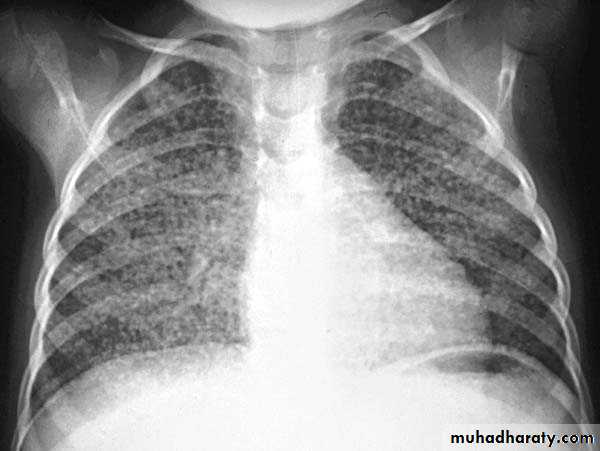

Right lower lobe consolidation

manifests as airspace shadowing that abuts the right hemidiaphragm,

obliterating the crisp margin of the hemidiaphragm and normal aerated lung.

bulging fissure sign refers to lobar consolidation where the affected portion of the lung is expanded. It is now rarely seen due to the widespread use of antibiotics.

The most common infective causative agents are :

Klebsiella pneumoniae